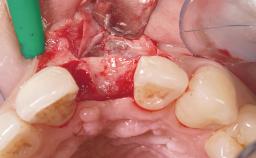

Late Placement of an Implant in a Maxillary Left Central Incisor Site

A 36-year-old female patient was referred for the replacement of the upper left central incisor (tooth 21), which had fractured. Although the tooth had been asymptomatic for many years, the crown began to loosen, at which time she presented to her dentist for an assessment. Teeth 21 and 22 had both been endodontically treated many years previously. She was a healthy individual and a non-smoker.

Bone Augmentation Horizontal|Staged

Bone Volume Deficient horizontally, requiring prior grafting